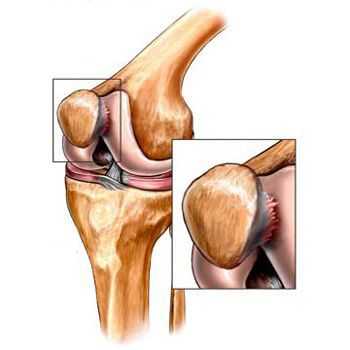

Повреждения менисков - нарушение целостности хрящевой прокладки, расположенной в полости коленного сустава. В остром периоде пациента беспокоит боль в колене и ограничение движений, отмечается блокировка сустава, отечность, возможно появление жидкости в суставе или развитие гемартроза. В последующем иногда наблюдаются повторные блокады, признаки воспаления, рецидивирующий синовит. Диагноз устанавливает травматолог на основании данных осмотра, анамнеза, в некоторых случаях - МРТ коленного сустава. Лечение включает устранение блокады, обеспечение полного покоя, по показаниям - пункцию сустава. При невозможности устранения блокады, повторных блокадах, сохранении болевого синдрома требуется операция.

Менисками называются хрящевые прокладки, расположенные внутри коленного сустава. Два мениска: латеральный (наружный) и медиальный (внутренний) находятся между суставными поверхностями большеберцовой и бедренной кости. Основные функции менисков – амортизация при беге и ходьбе. Кроме того, мениски выступают в роли стабилизаторов коленного сустава. Мениски эластичны и могут изменять свою форму во время движений в коленном суставе. Подвижность менисков неодинакова. Внутренний мениск связан с медиальной боковой связкой и менее подвижен, чем наружный, поэтому его повреждение возникает чаще.

По краям мениски срастаются с капсулой сустава и кровоснабжаются за счет сосудов капсулы. Внутренние части менисков не имеют собственных артерий и получают питание из внутрисуставной жидкости. Эта особенность питания обуславливает хорошее сращение менисков при краевых повреждениях и полное отсутствие сращения при повреждении внутренних частей.

Различают неполные, полные, поперечные, продольные («ручка лейки»), раздробленные и лоскутообразные разрывы менисков. Возможны повреждения менисков со смещением и без смещения оторванной части. Чаще всего наблюдаются продольные разрывы менисков по типу «ручки лейки». Реже встречаются изолированные повреждения заднего (25-30%) и переднего (9%) рогов. В результате повторных блокировок сустава при разрывах мениска возникают повреждения хряща внутреннего мыщелка бедренной кости (хондромаляция) и передней крестообразной связки.